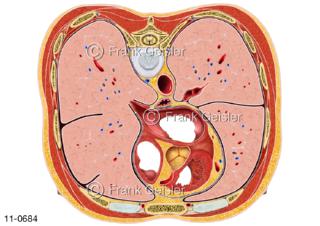

11-0684 Lunge und Organe im Brustraum, Rumpfquerschnitt Höhe Brustwirbel 7